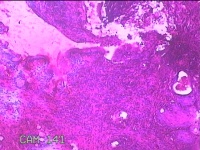

宫颈12点咬取物

性别

女

年龄

20岁

临床诊断

人乳头瘤病毒感染

一般病史

宫颈人乳头瘤病毒感染16型阳性。

标本名称

大体所见

灰白粉红色组织0.8x0.5x0.2cm一块。

慢性宫颈炎

慢性宫颈炎伴HPV感染